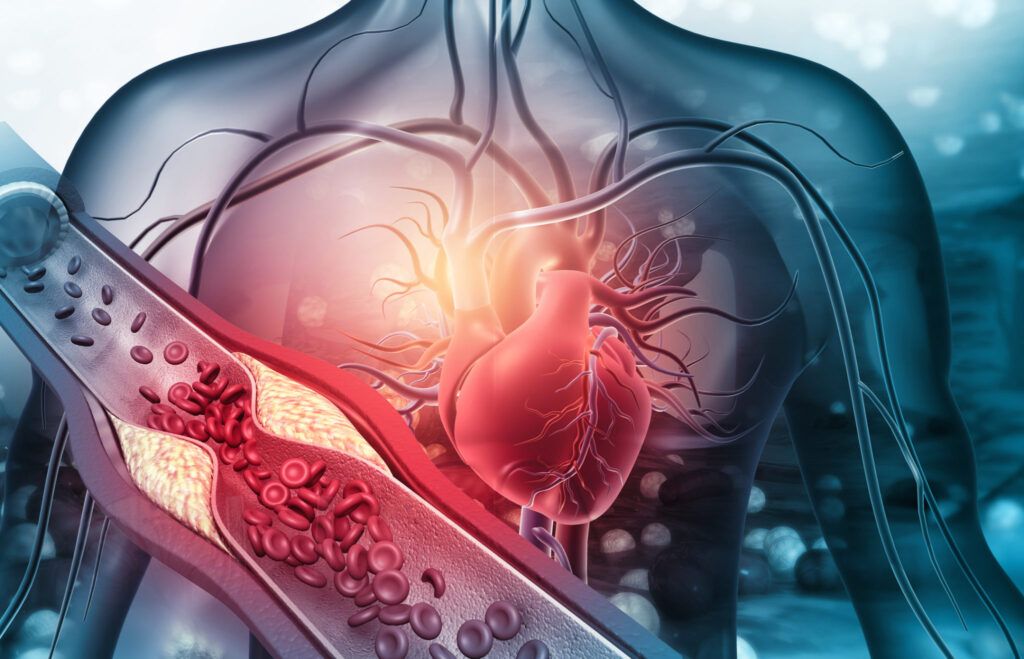

Ateroscleroza, principalul vinovat pentru afecțiunile cardiovasculare, este adesea rezultatul unor factori de risc modificabili. Hipertensiunea arterială, colesterolul crescut, fumatul, diabetul zaharat și obezitatea sunt doar câțiva dintre aceștia. Controlul greutății corporale, adoptarea unei diete echilibrate, renunțarea la fumat și gestionarea stresului sunt măsuri eficiente în reducerea riscului.